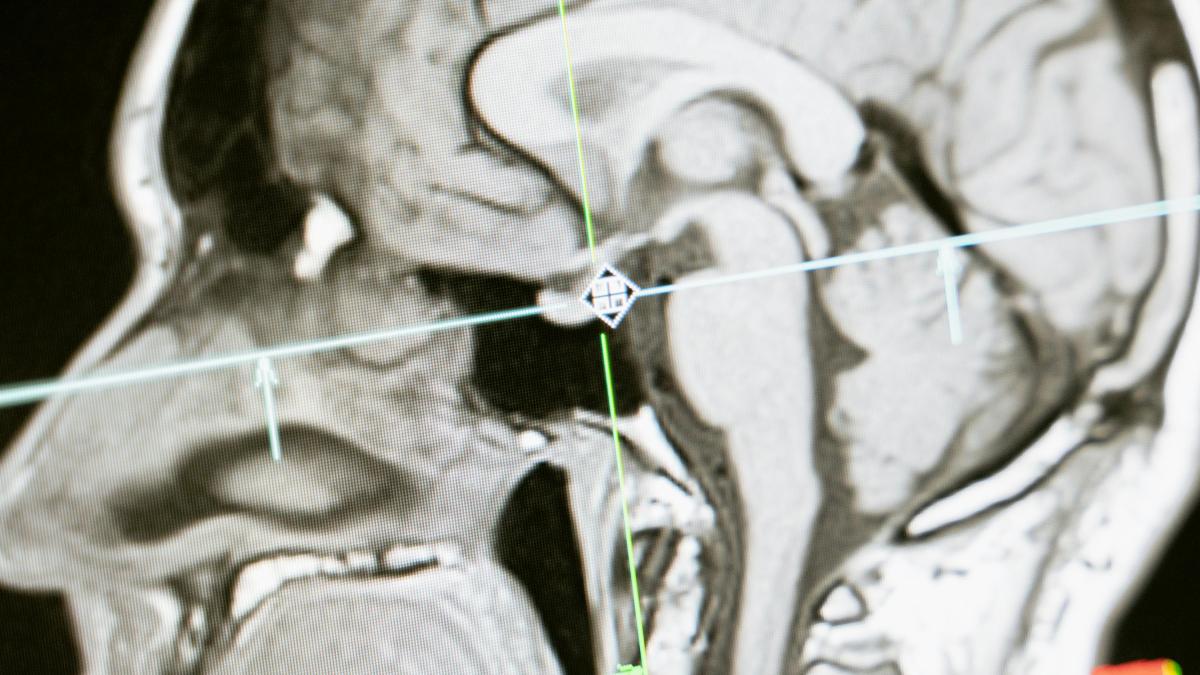

<![CDATA[Aprueban fármaco que detiene infartos cerebrales en un minuto]]>